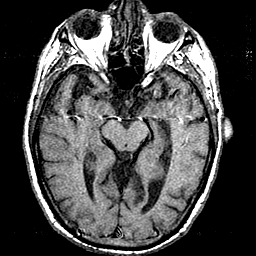

T1 - weighted MR -- Slice #19

[Home][Help][Clinical] Slice 19